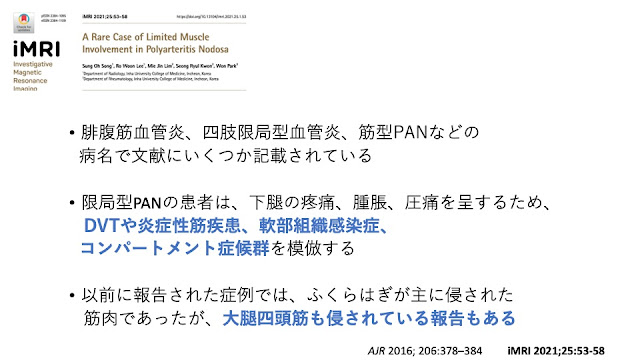

本症例は発熱はありませんでしたが、CRP上昇がありました

CTでは特別以上はありませんでした

本症例は大腿部の痛みが強く、MRIを撮像しました

そうすると、わずかではありますが、筋炎を疑う所見が見つかりました

造影MRIは他の症例報告と比べてみてもそっくりな画像でした

PETでも大腿の動脈に集積を認め、下肢限局型のPNに矛盾しませんでした

筋生検では血管炎の所見を証明することはできませんでしたが、

採取した部位が浅すぎて、血管炎を起こしている血管を拾えなかった可能性はあります

結局、下肢限局型のPNとしてステロイドで軽快しています